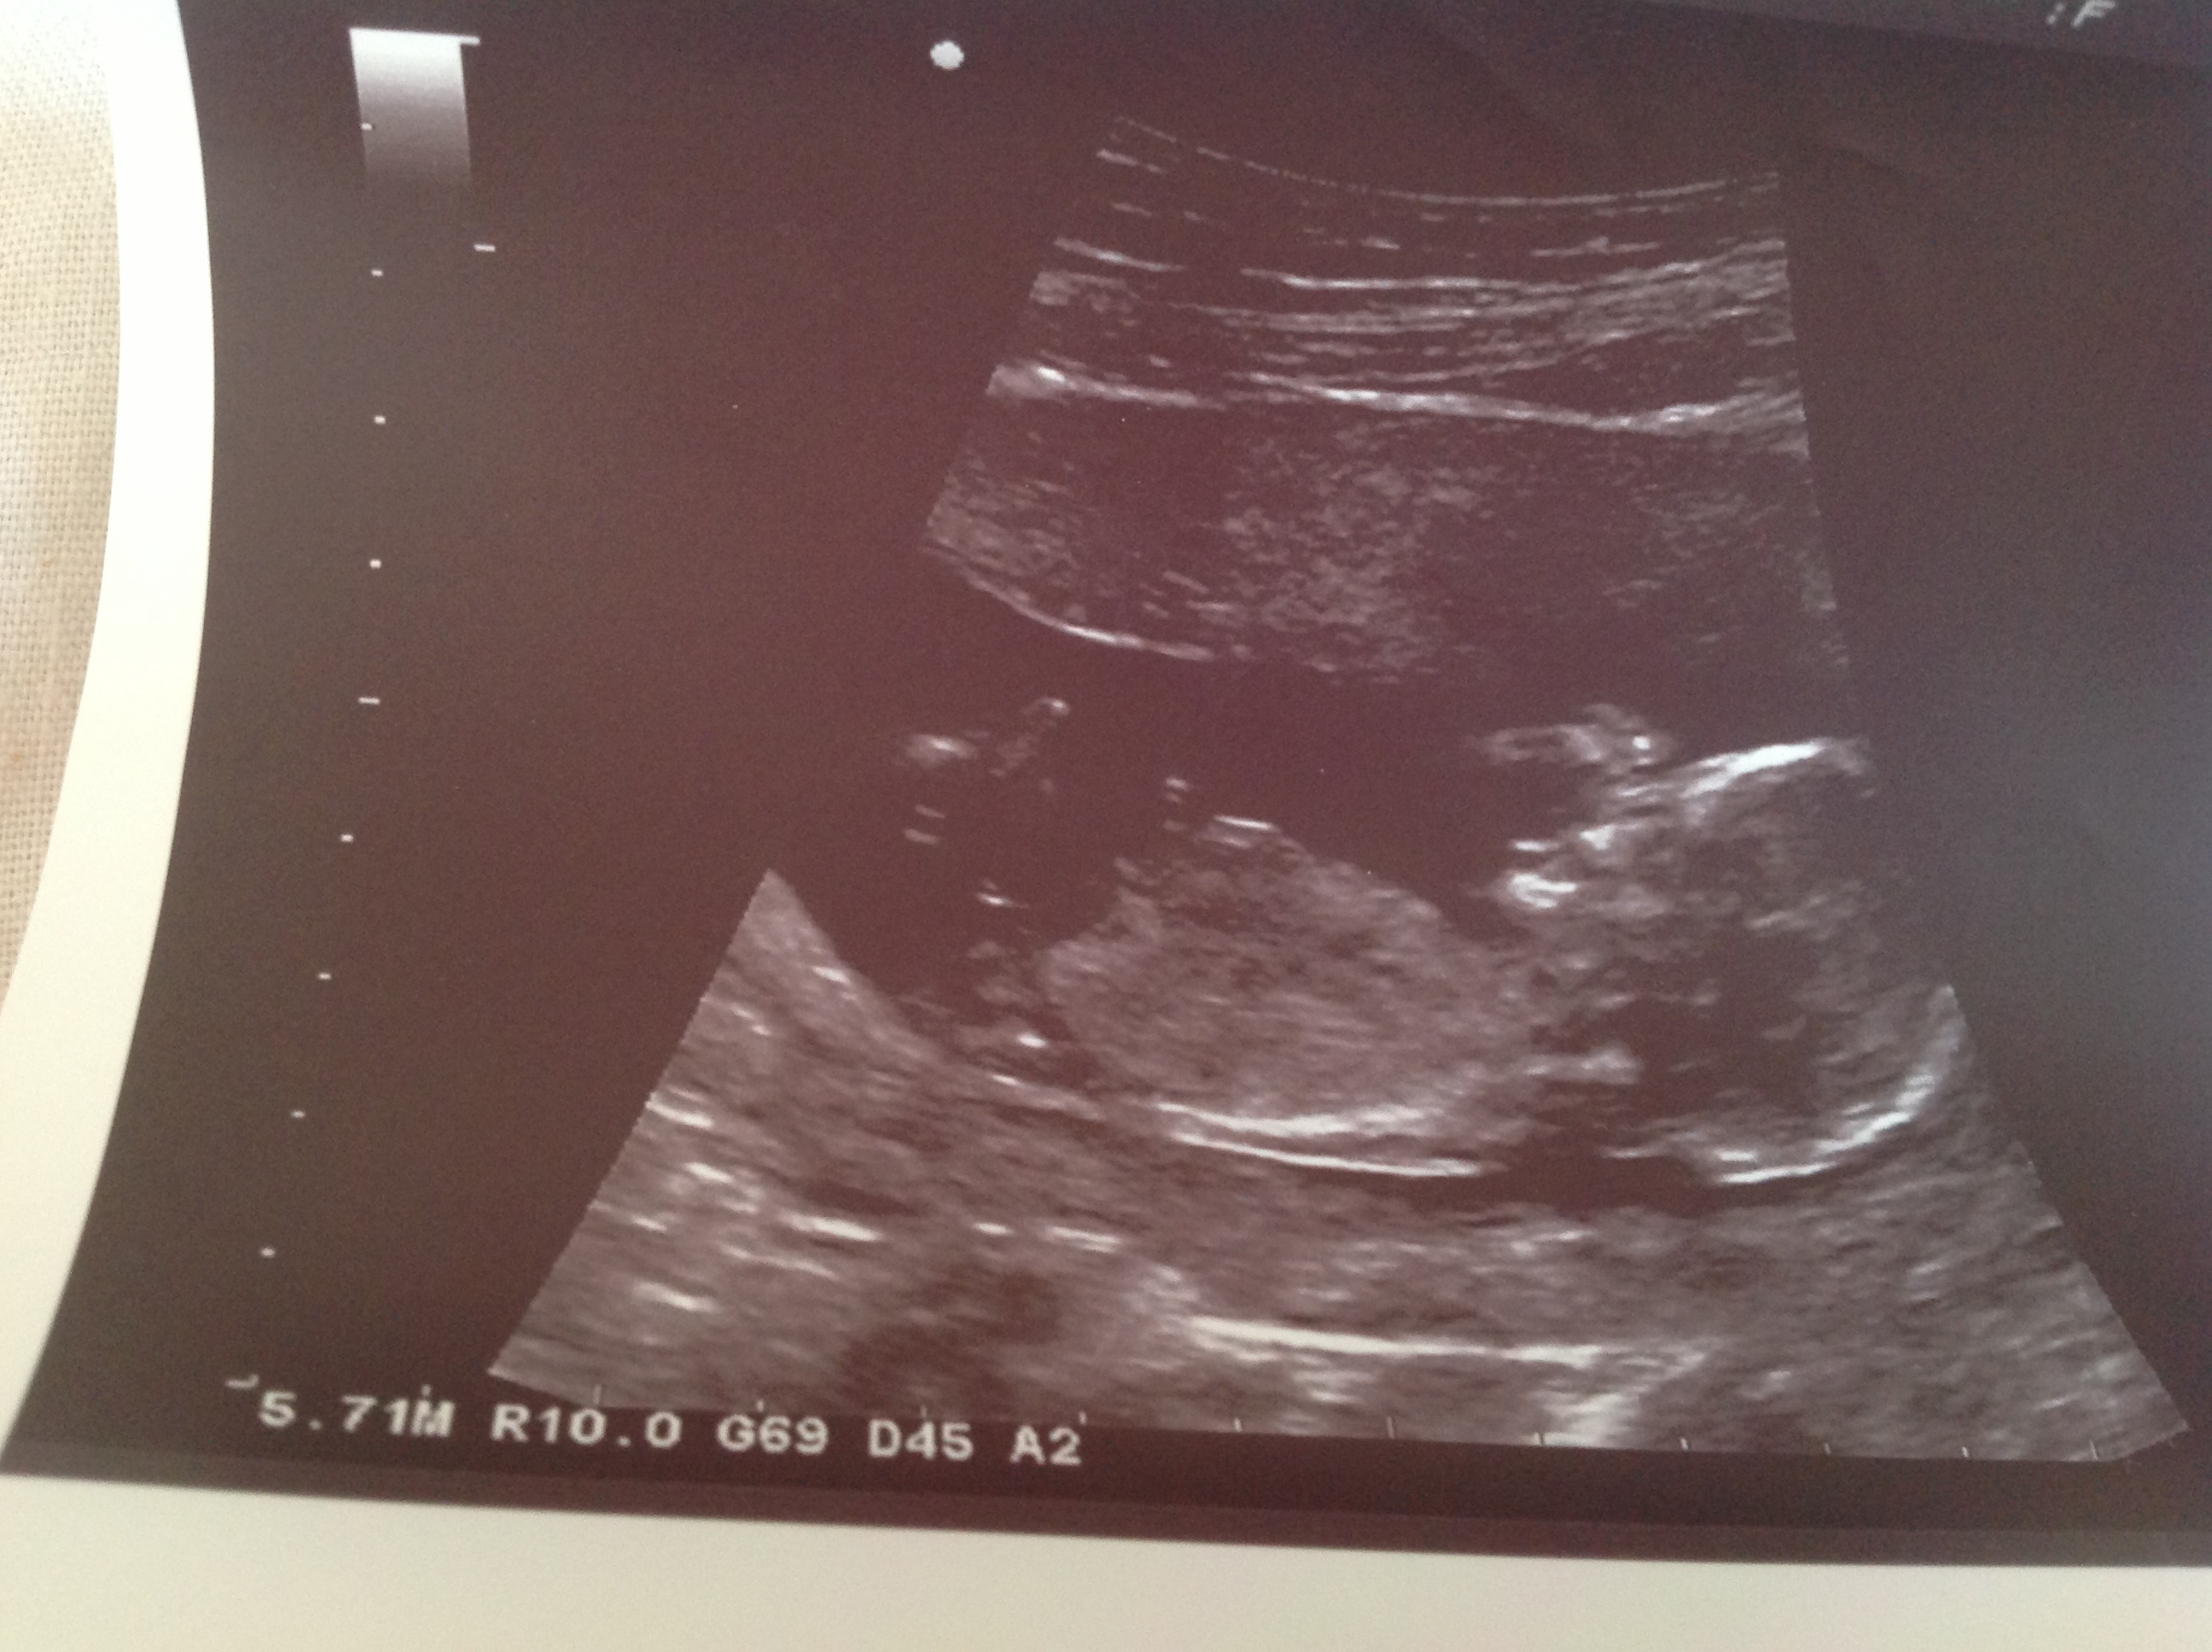

Attachment 11223Attachment 11224

Sorry I can't sew any clues.....congrats on baby tho :)

No nubs :(